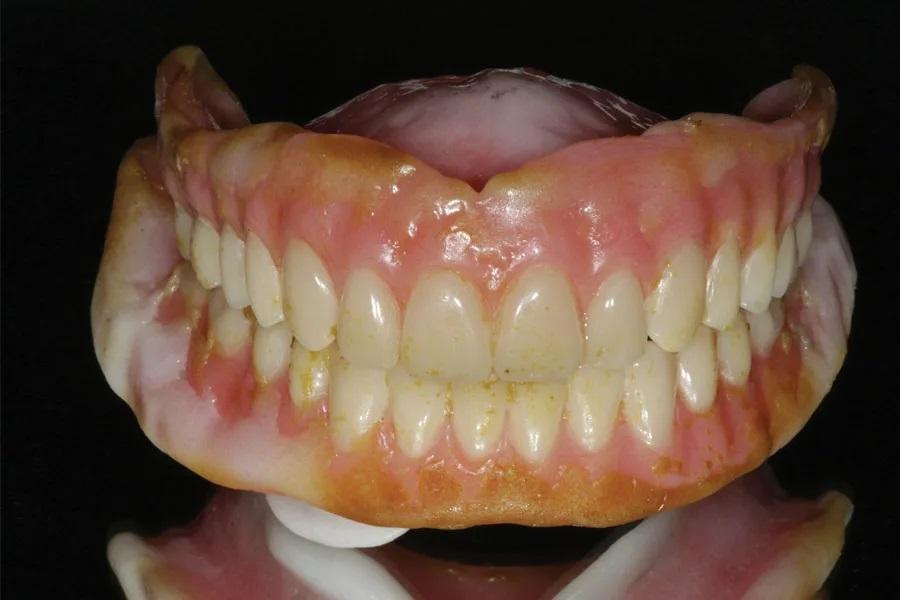

После полного заживления тканей (примерно через 6 месяцев) мягкая подкладка была удалена, и протезы были перебазированы материалом Hydro-Cast для функционального оттиска. Пациентка носила протезы 2 недели, после чего излишки материала были удалены, и протезы отсканировали для изготовления окончательных конструкций (Фото 7).

Фото 7: Отсканированные протезы с материалом для функционального оттиска.